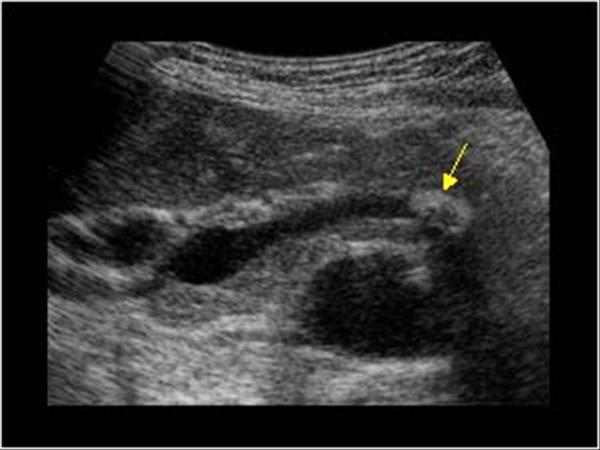

What is Polycystic liver disease?

This is an autosomal dominant genetic disease in which multiple small cysts cover the liver. 60% of patients with polycystic liver disease will have polycystic kidney disease.

What is the sonographic appearance of Polycystic liver disease?

Anechoic

Thin well-defined walls

Posterior

enhancement

Multiple

Varying in small size